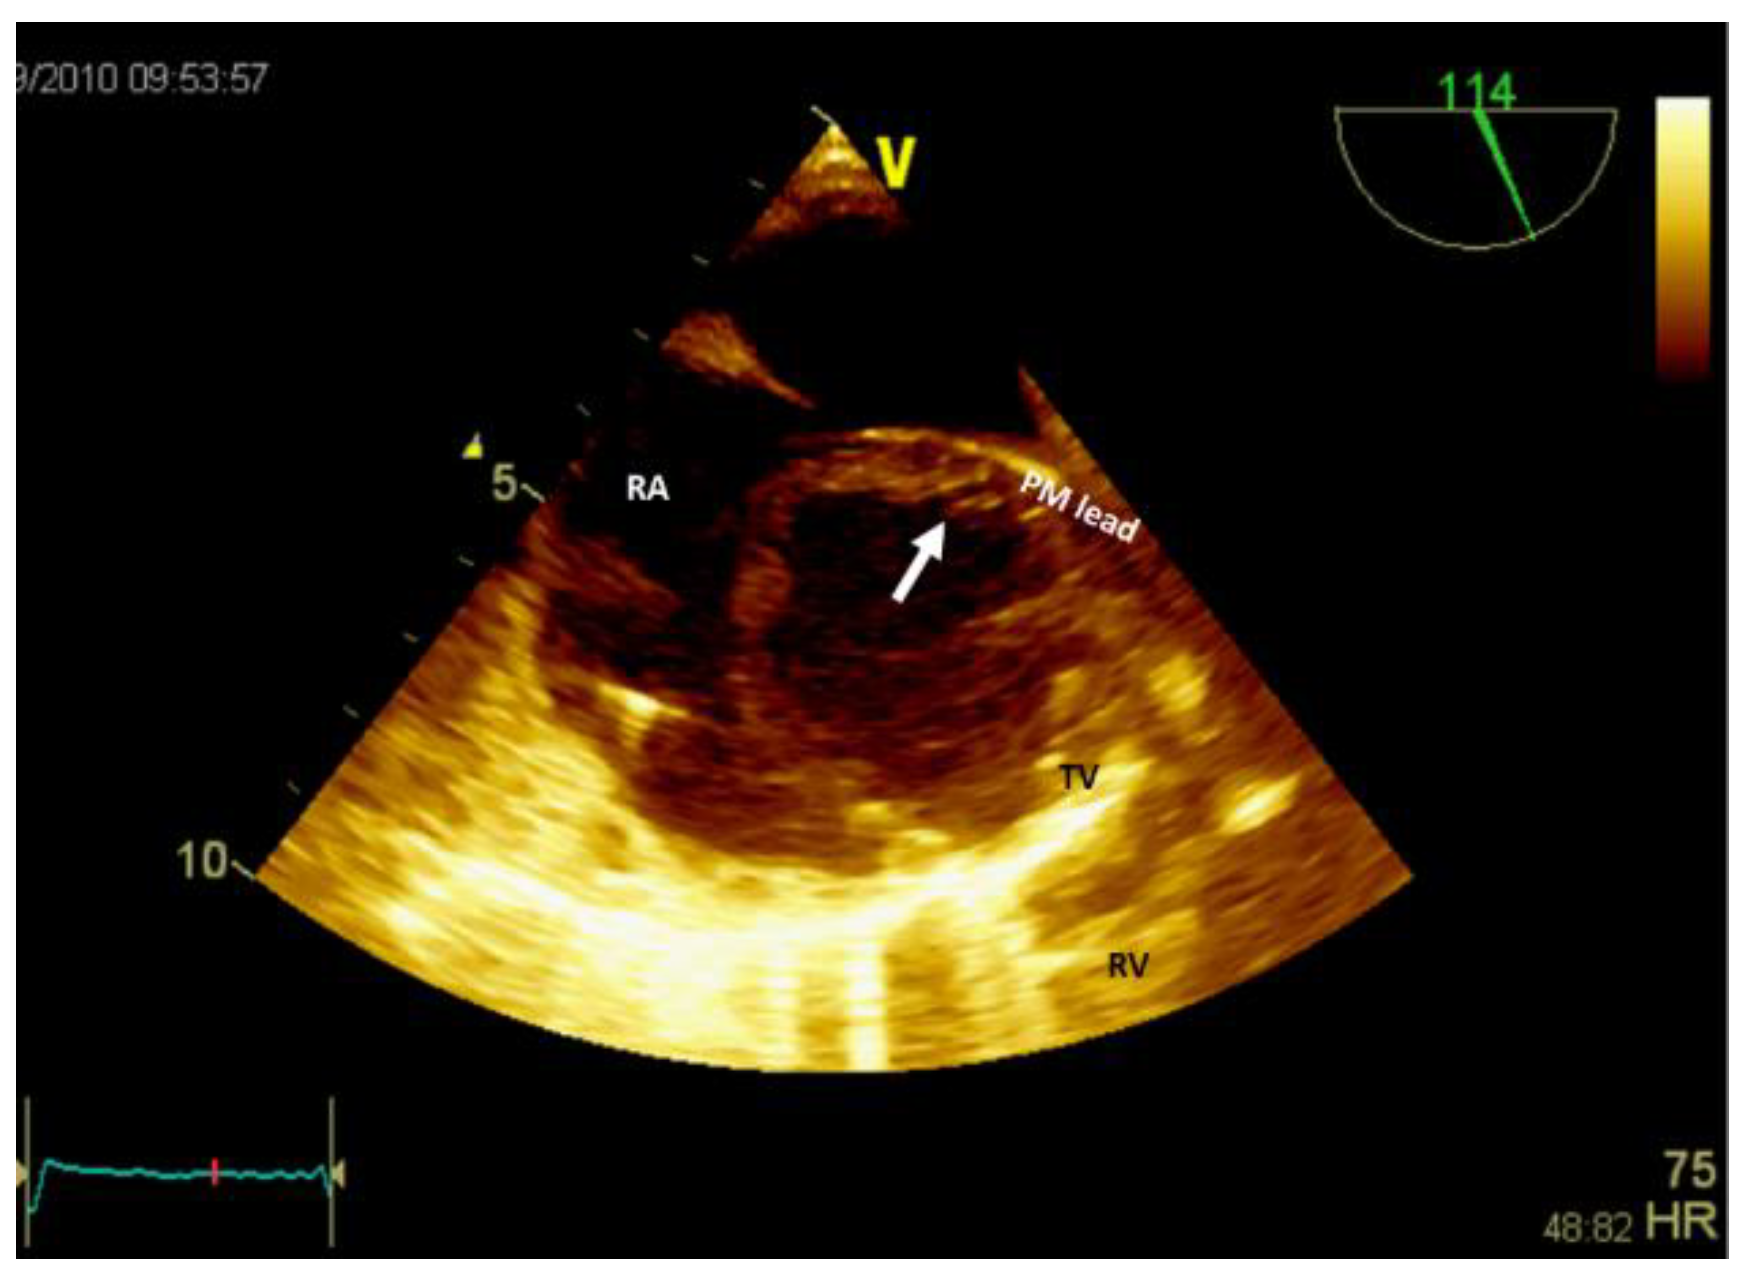

Figure 6. Bi-dimensional transesophageal echocardiography (short axis view at the level of great vessels) showing a mass in the right atrium, on the pacemaker leads. PM, pacemaker; RA, right atrium; RV, right ventricle; TV, tricuspid valve.

If the patient has a pacemaker or automatic implantable defibrillator, the first supposition in clinical suggestive context of endocarditis is a vegetation (Figure 6, Video S3 - Supplementary Materials). Differential diagnosis must include fibrin formations or thrombi. However, if the patient is already anticoagulated (due to atrial fibrillation) these diagnoses are less likely.